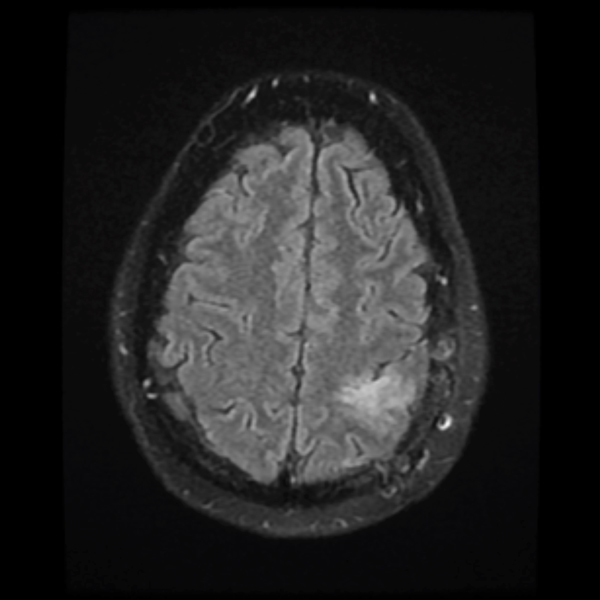

July 2019

A brain MRI showed an increased T2 signal in the left frontoparietal area. His tumor was non-enhancing. He underwent a partial resection of the tumor performed by NSPC neurosurgeon Ramin Rak, M.D., with intraoperative monitoring revealing eloquent motor cortex involvement anteriorly. The pathological diagnosis was WHO grade 2 oligodendroglioma.